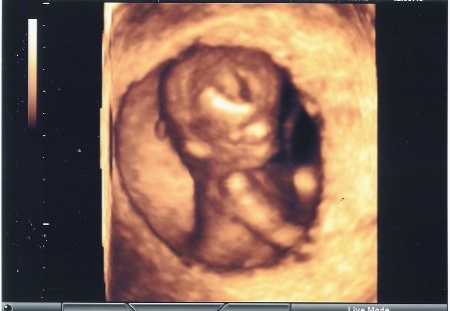

Falevél - íme a 12. heti 4D uh:

Kép Pocakmanó [/img]

Falevél - voltam már 4D-n a 12. héten, de akkor még nem érdemes, én a rossz tarkóredő eredmény miatt mentem, hogy mi az orvosnak a véleménye, szükséges-e a genetikai vizsgálat, vagyis Ő hogy látja és ha már ott voltunk akkor lett kép is. :lol:

Azt mondják a 16. hét után már biztosra meg tudják állapítani a nemét, én azt nagyon szerettem volna tudni, de azt így a genetikai vizsgálaton megtudtuk. De még egyszer el akarunk menni később, amikor már szépen látszik a baba arcocskája is. Ahogy Te is írod, amikor már több minden látszik! :lol: A 20. hét után már ez tényleg így van, de én majd csak a 28-30. hét körül gondoltam, hogy újra megyünk, mivel korai képem már van a kismanónkról. És akkor már cd-t vagy dvd-ti is is szeretnénk.

Szóval, ha semmi kényszer nem sürget akkor a 20 hét előtt semmi képpen nem mennék.

A 4D-hez annyit szeretnék hozzászólni, h nemrég a másik fórumon is téma volt. De ott is az jött le, és többektől ezt hallottam, ha 30.hét körül érdemes. Akkor még nem túl nagy a baba, viszont jól látszik mindene. Amikor még kisebb, akkor kevésé látszanak a részletek. És ugye a sok uh sem tesz ám jót a babának. A csak mozizást le kell redukálni. Viszont, ha vmi gond merülne fel, akkor ez a legmegbízhatóbb.

látom a 4D a téma.Csak javaslat, később 30-32 hetesen menjetek.Addig olyan kicsihogy sokszor nem látni semmit.Mi elmentünk 18 hetesen a Tankóhoz (igazából azért mert ez még genetikai UH és amit a kh-ban csinálnak "2 másodperc" alatt számomra nem túl meggyőző) és annyira belefúrta magát még a méhlepénybe hogy szinte semmi nem látszott.Viszont most voltunk 34 hetesen és már olyan kis kerek a pofija :lol: Csak kicsit mufurc volt :lol: Nem tetszett neki, pedig megbeszéltem vele hogy mosolyogni kell... :lol: